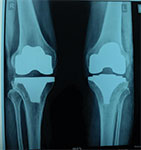

Case 7: Total Knee Replacement

54 years female was suffering from both knee pain for last 4-5 years. She had bilateral advanced osteoarthritis knee.

Patient underwent knee replacement surgery in two stages. 1st right knee was replaced after 8 months left knee was replaced.

X-RAY 1

knee advanced stage of osteoarthritis